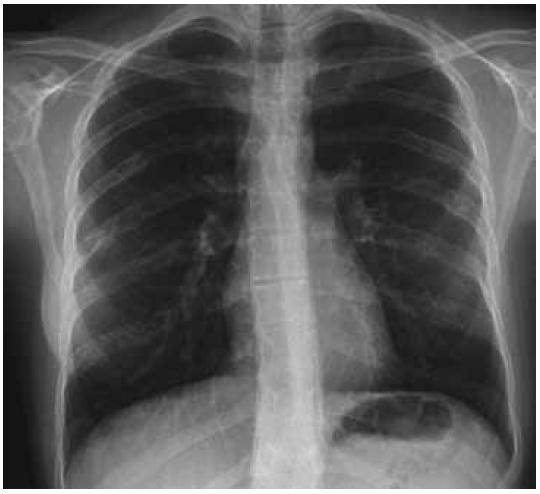

AP radiograph of the thorax showed areas of multiple lucent lesions with bony islands and linear sclerotic changes along the Ribs (Fig. 5). Lateral spine radiograph showed normal vertebral anatomy with no trace of osteogenic lesions (Fig. 6).

Fig. 6. Lateral spine radiograph showed normal vertebral anatomy with no trace of osteogenic lesions